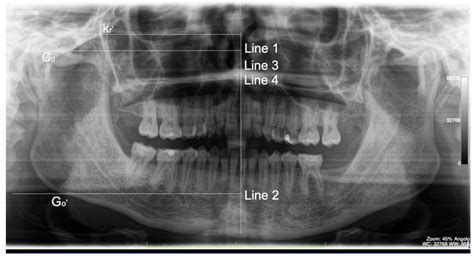

Imaging plays a crucial role in the evaluation of the coronoid process in mandible. Various imaging techniques can be employed to visualize the coronoid process and surrounding structures, aiding in diagnosis and treatment planning. Some of the commonly used imaging techniques include:

• X-rays: Plain radiographs can provide a basic overview of the mandible and the coronoid process in mandible. They are useful for detecting fractures, dislocations, and other bony abnormalities.

• Computed Tomography (CT) Scans: CT scans offer detailed cross-sectional images of the mandible, allowing for a more comprehensive evaluation of the coronoid process in mandible and surrounding structures. CT scans are particularly useful in cases of complex fractures or suspected pathology.

Prompt diagnosis and treatment of pathologies affecting the coronoid process in mandible are essential to prevent complications and restore function. Imaging techniques, such as X-rays, CT scans, and MRI, play a crucial role in the evaluation of these conditions, aiding in diagnosis and treatment planning.